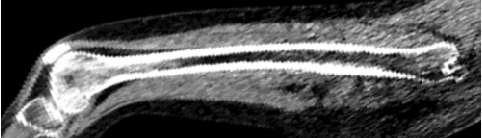

Bone segmentation from CT images is a task that has been worked on for decades. It is an important ingredient to several diagnostics or treatment planning approaches and relevant to various diseases. As high-quality manual and semi-automatic bone segmentation is very time-consuming, a reliable and fully automatic approach would be of great interest in many scenarios. In this publication, we propose a UNet inspired architecture to address the task using Deep Learning. We evaluated the approach on whole-body CT scans of patients suffering from multiple myeloma. As the disease decomposes the bone, an accurate segmentation is of utmost importance for the evaluation of bone density, disease staging and localization of focal lesions. The method was evaluated on an in-house data-set of 6000 2D image slices taken from 15 whole-body CT scans, achieving a dice score of 0.96 and an IOU of 0.94.